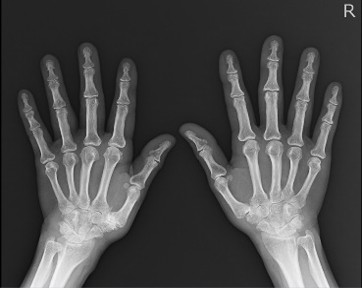

X線撮影室

胸部・腹部および全身骨部のX線撮影を行っています。

撮影部位によって着替えをお願いしています。

湿布・カイロ・アクセサリー等は外していただく場合があります。